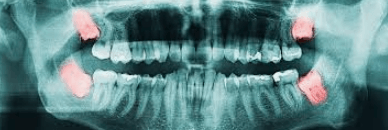

X-Rays (if they are given to you)